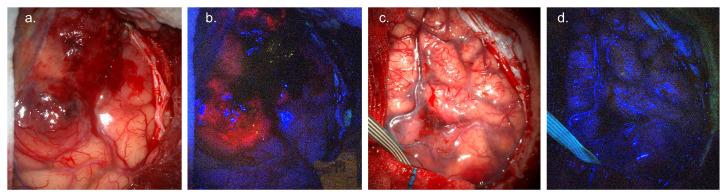

Fluorescence-guided surgery (FGS) was pioneered for glioma and is now established as the standard of care. Gliomas are infiltrative tumours with diffuse margins. FGS provides improved intra-operative identification of tumour margins based on tumour-specific emission visible to the operating surgeon, resulting in increased rates of gross total resection. Multiple fluorescence agents may be used including 5-ALA, fluorescein sodium, and indocyanine green (ICG). This review details the indication, required equipment, mechanism of action, evidence base, limitations, and regulatory issues for each fluorophore as utilised in current clinical practice. FGS for glioma is limited by a reliance on subjective interpretation of visible fluorescence, which is often not present in low-grade glioma (LGG) or at the infiltrative tumour margin. Consequently, there has been a drive to develop enhanced, objective FGS techniques utilising both quantitative fluorescence (QF) imaging systems and novel fluorophores. This review provides an overview of emerging QF imaging systems for FGS. The pipeline for novel fluorophore development is also summarised.